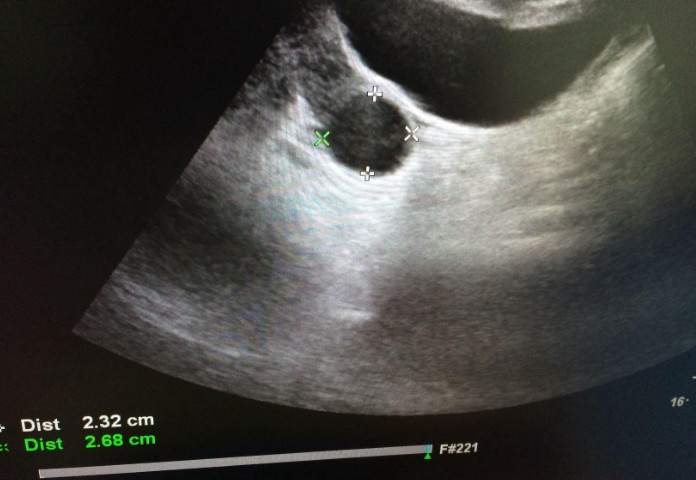

例假第二天左右两侧窦卵泡数量一共9个正常吗?

例假二天左右两侧窦卵泡数量一共9个正常是正常现象不用太担心,在来例假的第二天两侧窦卵泡数量在5-12个都处于正常范围,不会影响到之后的正常生育,如果低于5个的话就要考虑是不是卵巢早衰或者其他病变的问题了。女性两侧窦卵泡数量会根据不同的时间会发生不同的变化,有时候多有时候少重要上在每个时间段内处于正常的范围及没有任何问题,比如:年龄卵泡数量卵泡质量20-30岁15-25个高31-35岁10-20个一